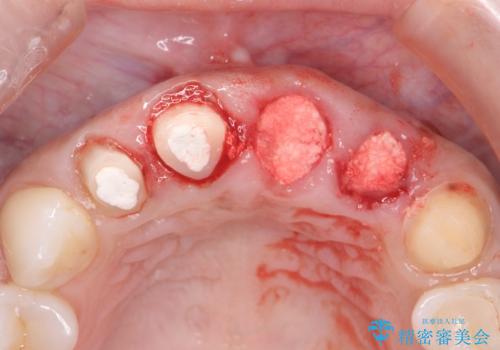

一見して問題ないように見える左側の2前歯は、セラミックを除去してみると亀裂や虫歯の再発が見られました。

抜歯時に可及的に歯肉のボリュームを保つよう骨充填材とコラーゲン製剤による填塞を行い審美的かつ機能的なブリッジとなるよう治療を進めます。

一件綺麗に見えるセラミックも適合や精度が悪いと、内部で虫歯が進行し亀裂や破折、悪臭の原因となることがあります。